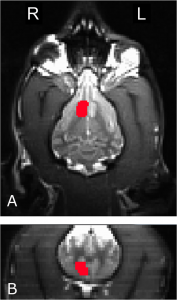

Upon accumulating data, the team analyzed the BOLD (blood oxygen level dependent) response in each dog’s caudate nucleus, an area of the brain that activates upon the commencement of the anticipation of reward. The key measurement of interest was the delta in caudate activation between the no-reward and reward states within each of the three different case states. The team then compared the fMRI results to the personality profiles of each dog as determined by the standardized C-BARQ test developed by the University of Pennsylvania. The results showed that service dogs had a much stronger response to Case 1 in comparison to other dogs and in comparison to the other states. In contrast, dogs with a history of aggressive reactivity tended to respond most significantly to Case 2, when a stranger communicated a reward signal, most likely because the dogs felt safer in the stranger state only when the person’s presence was accompanied by the reward signal and the knowledge that a treat receipt was imminent.